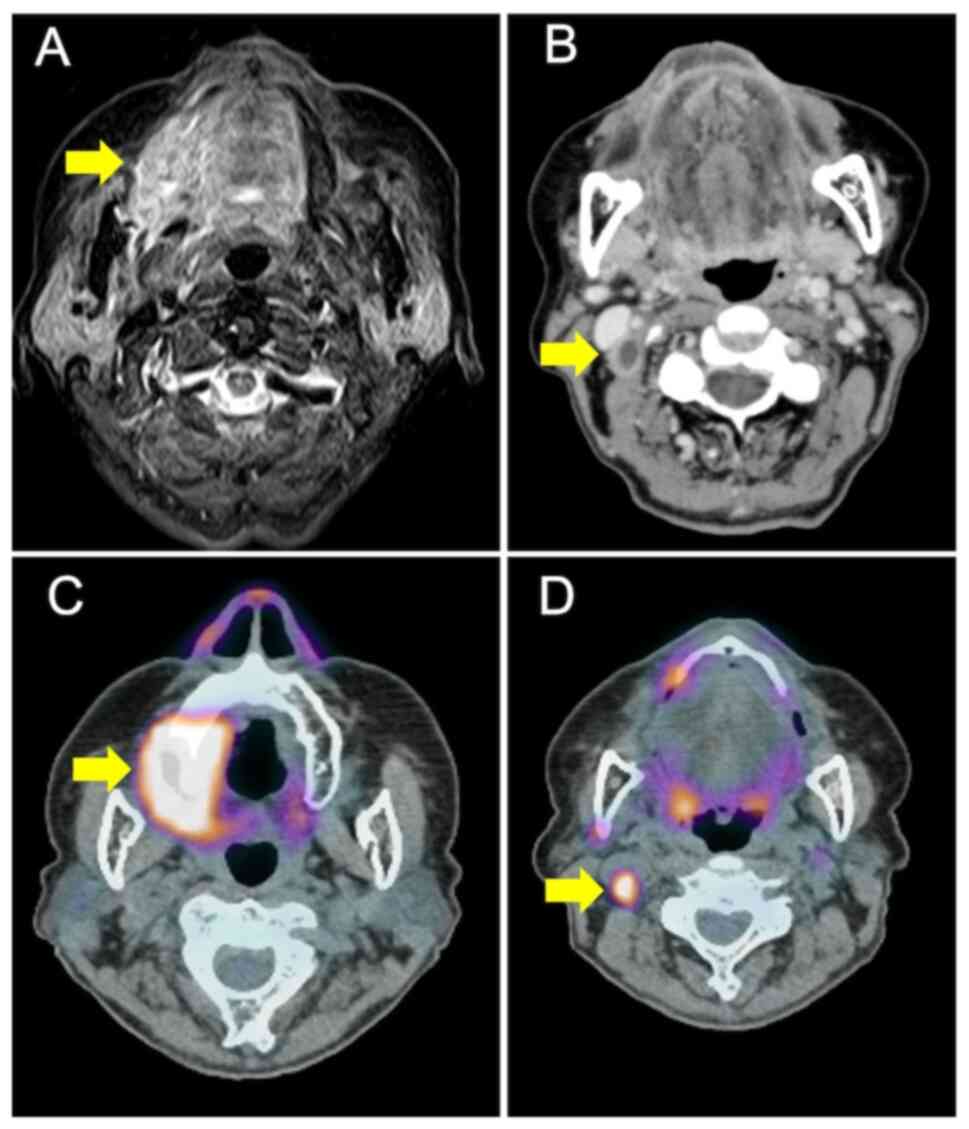

The ECAS system can superselectively administer anticancer drugs to numerous feeding arteries from the superficial temporal artery: A case report and literature review

Superselective intra‑arterial chemoradiotherapy (SSIACRT) is one of the curative treatments for advanced oral cancer. SSIACRT can reportedly treat cervical lymph node metastases in the level I‑IIA area by super selectively catheterizing the facial artery (FA) and infusing drugs. However, since advanced oral cancer lesions involve a number of feeding vessels, retrograde treatment requires the placement of catheters from the superficial temporal artery (STA) and occipital artery (OA). Furthermore, in the case of level IIB lymph node metastasis, the catheter must be changed because it is necessary to administer anticancer drugs to more than three routes, including the OA, when the feeding arteries of the primary tumor are combined. The external carotid artery sheath (ECAS) system used in the present study involves the insertion of a microcatheter or steering catheter from one route of the STA, allowing selection of numerous feeding vessels, including the OA. The ECAS system can facilitate the administration of chemotherapy via the STA simultaneously to the maxillary artery, lingual artery, FA and OA. The present study describes cases of maxillary gingival cancer and tongue cancer with cervical lymph node metastasis, which were treated with the ECAS system via the STA; the treatment successfully controlled both the primary tumor and cervical lymph node metastasis. In the two cases described in the present study, metastatic lymph nodes were found in the level ⅠB and ⅡB region, but were successfully treated by administering cisplatin via the OA, in addition to the primary lesion. To date, to the best of our knowledge, there is no case report clearly referring to the treatment of lymph node metastasis using the ECAS system. In conclusion, SSIACRT using ECAS may be considered a useful treatment for oral cancer with cervical lymph node metastasis.